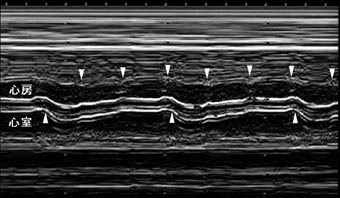

完全房室ブロック

心房収縮(下向矢頭)および心室収縮(上向矢頭)が認められ、両者は無関係に出現する。

心房収縮数は140/分で胎児心拍数は48/分である。

心房収縮数は140/分で胎児心拍数は48/分である。